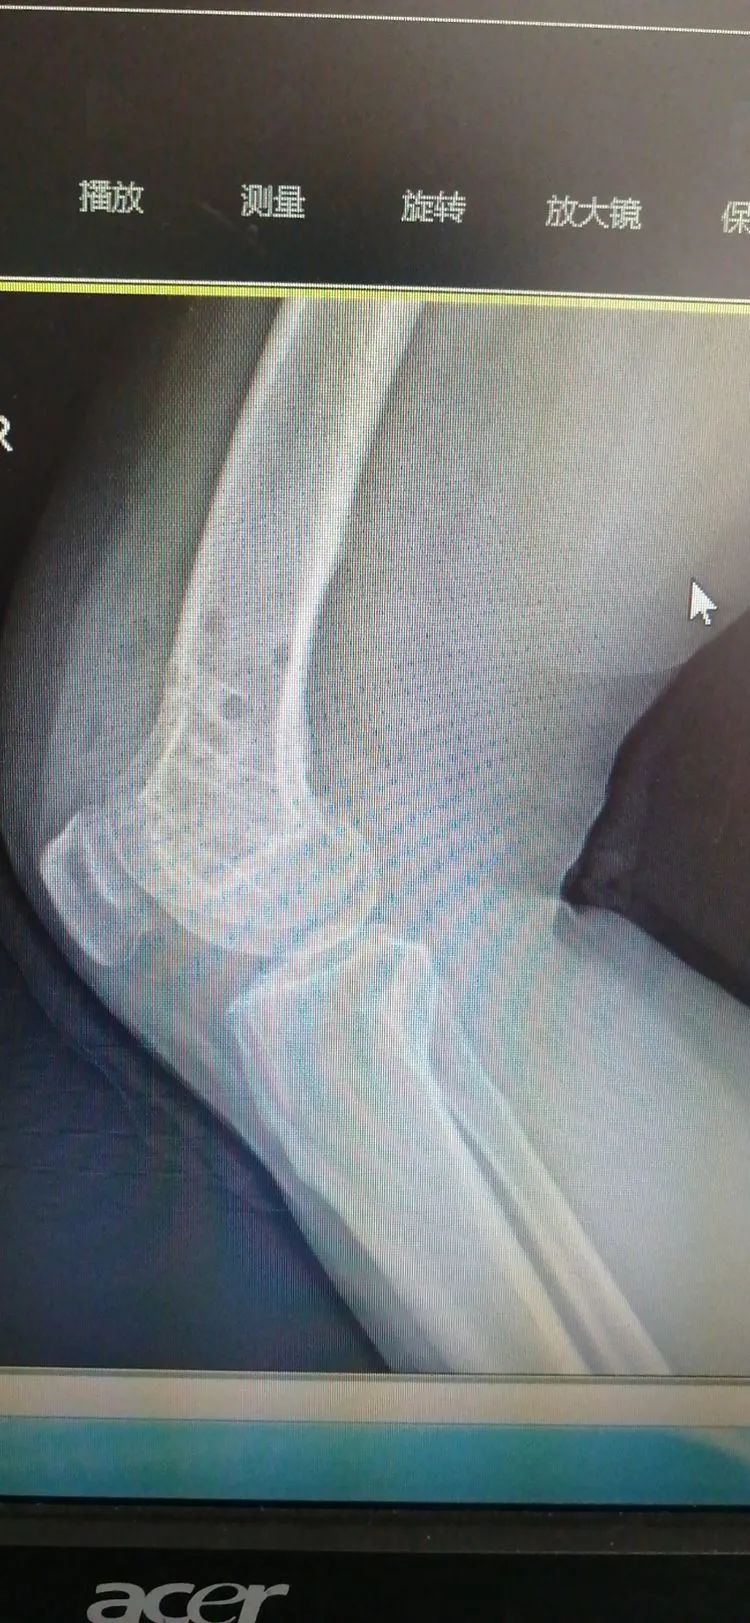

患者女性,49岁,跌伤致右膝肿痛、活动受限入院。拍片提示股骨髁间骨折,关节面不平整,不稳定骨折,有明确手术指征。

术中镜下见骨折累及关节面,关节面不平整,呈阶梯样改变

复位固定后,镜下见关节面已平整,最大程度减少此类骨折导致的关节磨损,改善预后。

术后拍片示骨折对位对线好,关节面平整